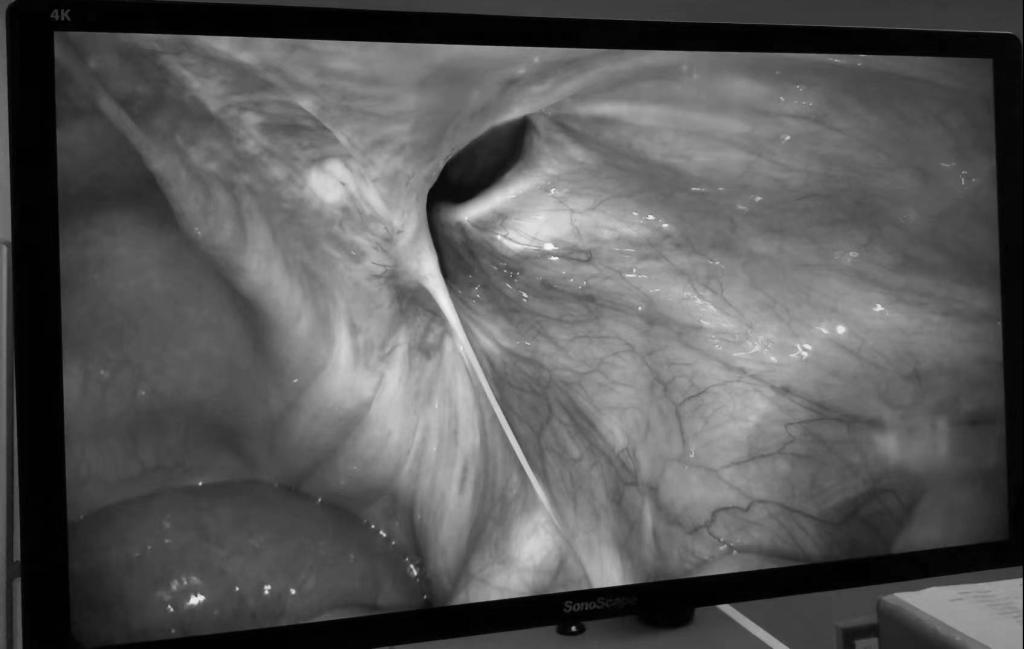

手术如期进行,术中发现在同一侧合并有两处腹股沟疝(斜疝+股疝),疝囊位于右侧腹壁下动脉外侧,内环口约2×2cm,进入阴囊,成螺旋状自外向内并与脐旁韧带及股管相连,疝囊大小约4×3×2cm,同时合并股疝,这在术前的常规检查中难以发现,腹膜粘连严重使得游离难度大大增加。若按照术前判定的情况进行修补,很可能导致修补范围不足,后期再出问题。不过在孙宏伟主任专业决策下和精湛的手术技艺下,历经1.5个小时,最终顺利完成了腹膜前间隙的游离,成功放置补片进行了修补,将两处疝一同修补。且手术伤口小,极大减少了靳大爷的痛苦,缩短了恢复时间。患者术后生命体征平稳,术后第一天即可下地活动。

(图片来源于网络)